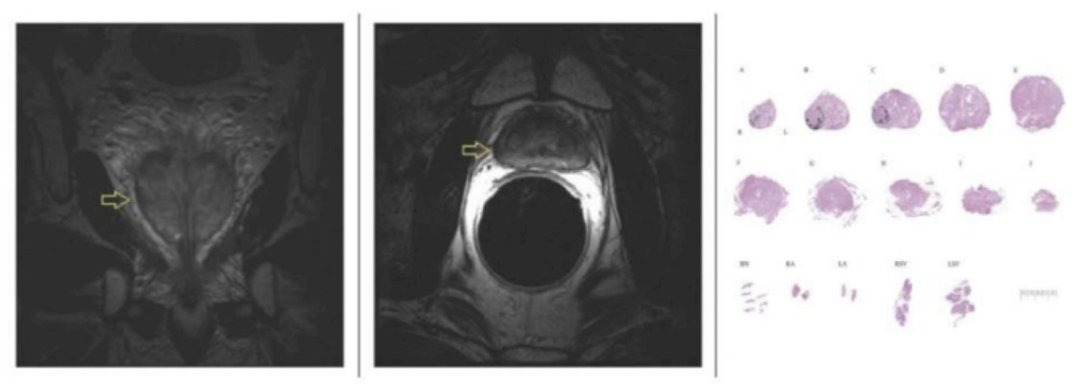

1/4 Delighted to share in print @EurUrolFocus @aleczhu @mostrasser @TimMcClureMD @SGereta @eemilycheng @WeillCornell @WCMUrology: the1st comparative study of focal therapy (Cryo n=75) vs radical prostatectomy (n=298) for GG2 and GG3. sciencedirect.com/science/articl…